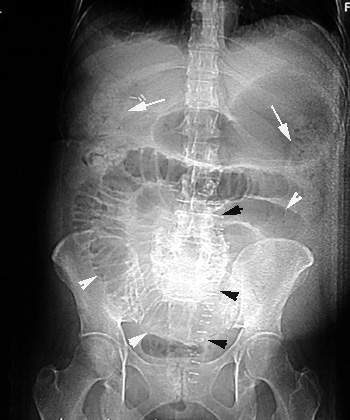

Plain film in a case with Small bowel obstruction

Post-Op Paralytic Ileus

- Multiple dilated small bowel loops are seen (white arrowheads).

- There is fecal material in the right and left colon

(arrows).

- Air is seen in the rectum.

- The surgical staples indicate recent abdominal surgery. (black arrowheads).

|